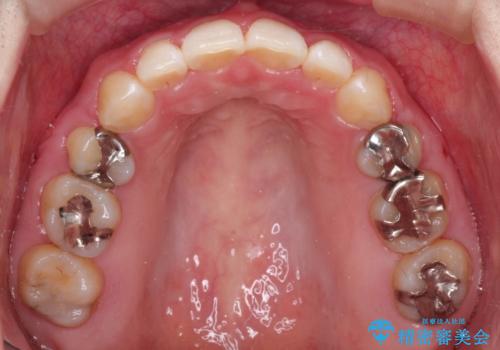

- 口が閉じずらく、口元が突出している状態でした。

上下左右の歯を1本ずつ、合計4本抜歯して、ワイヤーにて矯正することとなりました。

もともと下の前歯の永久歯が1本欠損しており、抜歯部位の選択を考慮しなければならない症例でした。シミュレーションを事前に行い、下顎の抜歯部位を決定しました。